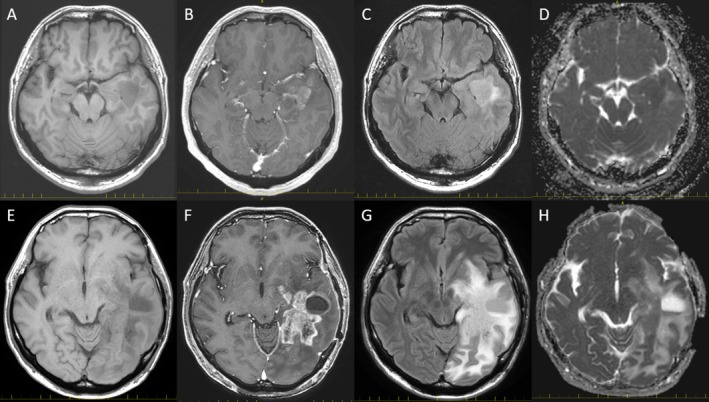

Diffuse hemispheric glioma, H3 G34-mutant (DHG), is a newly defined pediatric-type tumor in the 2021 WHO classification of central nervous system (CNS) tumors. DHGs harbor missense mutations at codon 35 of H3F3A (H3.3 G35R/V mutations) and exhibit diverse histopathological features, such as glioblastomas or CNS embryonal tumors. Regardless of histological variation, they demonstrate uniform immunohistochemical and molecular findings: Olig2 negative, ATRX loss, p53 positive, and MGMT promoter methylated. These tumors occur predominantly in the cerebral hemispheres of adolescents and young adults, while they are extremely rare in middle-aged and elderly individuals. Here, we report a middle-aged case of DHG with prominent perivascular invasion. The tumor initially demonstrated a focal glioblastoma-like area, whereas the recurrent tumor predominantly showed perivascular spread of spindle cells. We reviewed previously reported DHG cases in middle-aged and elderly patients and compared their clinicopathological features with those of adolescents and young adults.